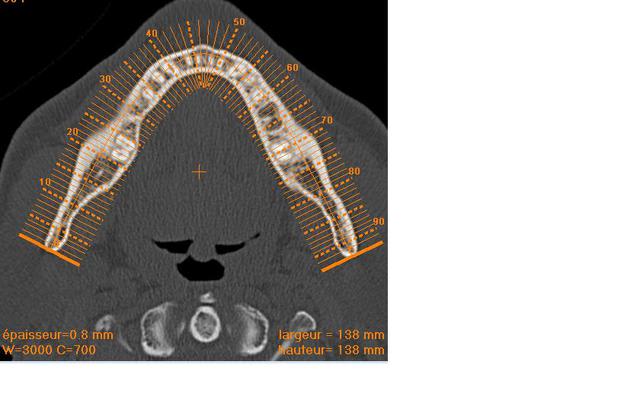

Deux implants en 36 46 et j'espere vous avoir donné les bonnes coupes sinon cela veut dire que je n'ai rien compris !!!

j' ai fais des mesures avec le logiciel pour un implant de 12 mm

sur les bonnes coupes je l'espere ;)